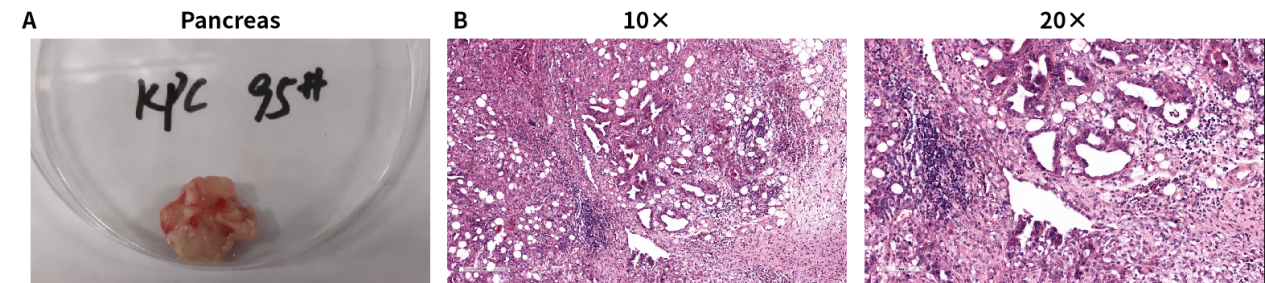

KPC小鼠是目前成功建立的一种胰腺导管腺癌模型小鼠,具有很多与人胰腺癌相似的特点,如胰腺内皮细胞瘤形成,强烈的免疫反应等。80%的KPC小鼠出现了肝转移和肺转移的现象。KPC小鼠包含了Kras和Trp53基因突变;而在人胰腺癌的研究中发现,分别有80%和70%的患者表达这两种突变蛋白。 KPC小鼠的p53基因含有一个显性抑制性点突变(p53-R172H ),Kras基因含有一个条件性活化点突变(Kras-G12D)。模型中,Kras突变基因的上游含有lox-stop-lox终止序列,其在没有Cre重组酶的条件下是不表达的。将Cre重组酶连接到Pdx1的启动子后,其将在胰腺的腺泡、胰岛和导管中表达。

图6. KPC小鼠模型的自发式性胰腺癌体和HE染色结果。胰腺表面不平整,多个结节状突起;细胞排列无序,组织结构呈不规则细胞团,可见胰腺导管增生,炎症细胞浸润,间质纤维形成,符合肿瘤组织结构特征。